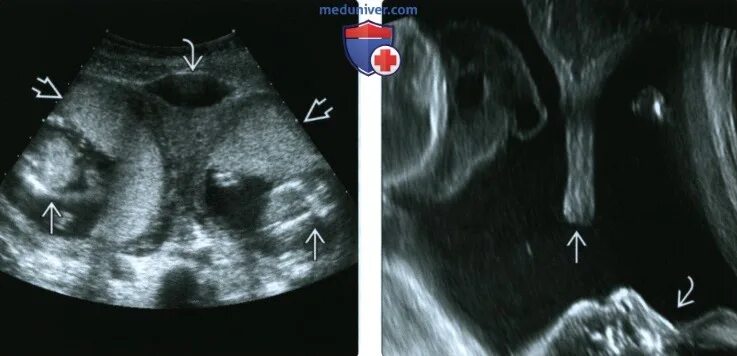

Аномальная беременность